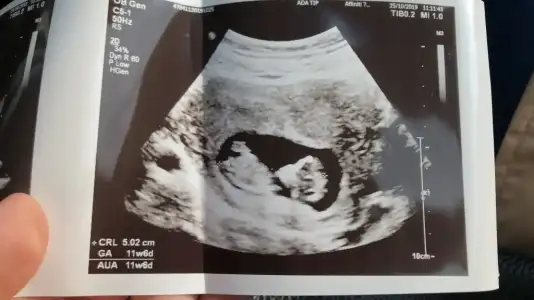

Merhaba bizim bebiş ters duruyor secde pozisyonunda ultrasona göre 12+3 benim bebişim içinde bir tahminde bulanabilirmisiniz rica etsem.

Eklentiler

• 20191030_174024.webp

20191030_174024.webp

24,7 KB · Görüntüleme: 63